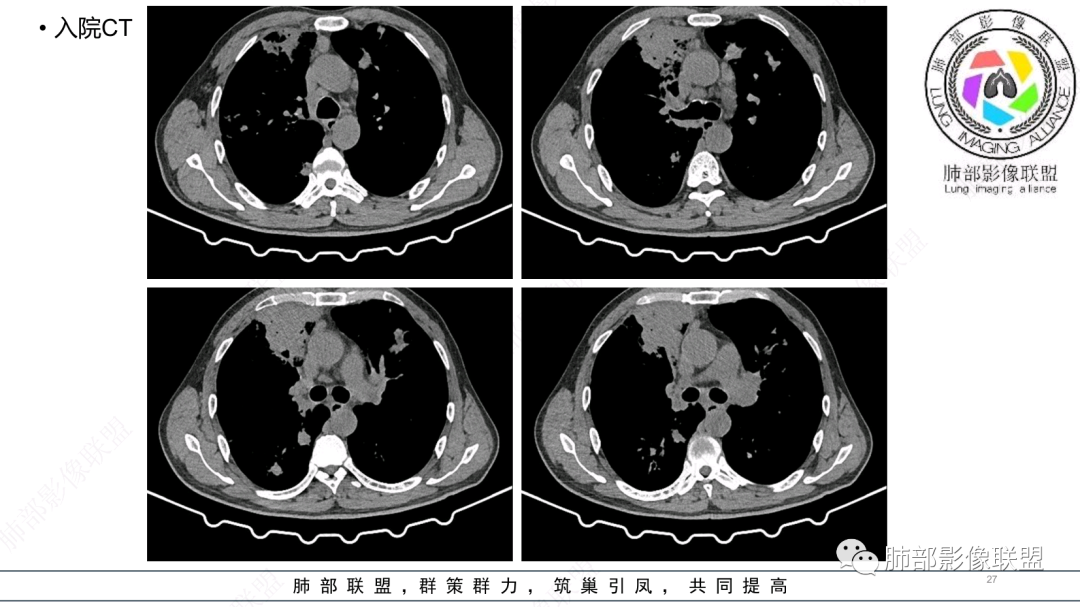

56岁,工作性质:环卫工人。主诉:咳、痰、喘、发病一周。急性起病(或者慢病+AE),呼吸道感染症状。化验指标白细胞、中性、CRP明显升高。影像学显示多灶性,有柱状支扩,囊状支扩等结构肺病,责任细菌主要考虑铜绿假单胞菌,不排除合并其他细菌以阴杆为主;存在树芽影,发热,炎症沿支气管束分布,是否合并TB?真菌?;树芽伴发热支原体感染也要需要考虑进去;全肺多灶性炎症,部分病灶周围有晕,右上叶疑似反晕,内部疑似有丝,右下肺考虑存在粘液栓,加之环卫工工作性质,考虑霉菌,主要考虑曲霉。

两肺支扩,两肺沿支气管分布多发结节、树芽及团块,边缘模糊,部分支气管管壁增厚,考虑气道侵袭性曲霉菌,鉴别铜绿、奴卡、结核。

支气管壁增厚,晕征明显,病灶沿着支气管纵向分布,结合患者职业,考虑气道侵袭性曲霉。

多发结节,部分结节边缘清楚,部分边缘模糊,支扩合并肉芽肿性炎,奴卡菌与曲霉之间选择。

影像改变为支扩伴气道来源感染,部分实变性伴有小脓肿及钙化,结合PCT及白细胞、中性粒明显增高,符合细菌感染,首先考虑奴卡,绿脓次之,因为临床有喘息、影像实变性有钙化,加上环卫工这一职业史,需要鉴别曲霉或奴卡合并曲霉。

支扩伴发的铜绿主要是支气管周围的渗出改变,不会伴有肉芽肿改变,但是如果是长期反复慢性感染的铜绿合并一些机化的时候影像上也可以类似肉芽肿,但是这种很少见,而且机化一般会有纤维化,也容易与肉芽肿区分,而支扩伴发奴卡即可以有渗出,也可以有肉芽肿和慢性或亚急性脓肿出现,所以今天这个肯定是考虑奴卡的。